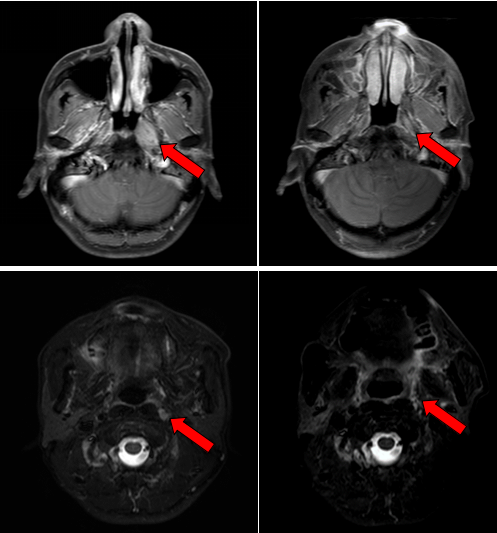

治疗前后鼻咽部病灶、咽后淋巴结病灶对比( 左:治疗前,右:治疗后)

2016年7月,患者因左侧耳鸣一个多月到医院就诊,经过一系列检查,最终确诊为鼻咽非角化性癌,分期为T3N1M0 Ⅲ期,属于局部晚期鼻咽癌。我院鼻咽癌诊治中心邱素芳主任医师团队接诊后,为其量身制定了“诱导化疗+同步放化疗+辅助化疗”综合方案,在放疗环节凭借精细靶区勾画与剂量调控,实现“精准打击”。治疗结束后复查,肿瘤已基本退缩。

2018年2月,复查MRI提示颈部淋巴结复发,患者在我院接受了淋巴结清扫术;2020年1月,胸部CT提示肿瘤转移至双肺,病情出现进展。医疗团队启用“晚期肿瘤布拉格治疗”方案,这一创新疗法融合了精准的局部放射治疗、GM-CSF刺激骨髓抗原释放技术,并联合免疫治疗,三管齐下。在完成14个周期治疗后,肺转移灶的代谢活性显著降低。